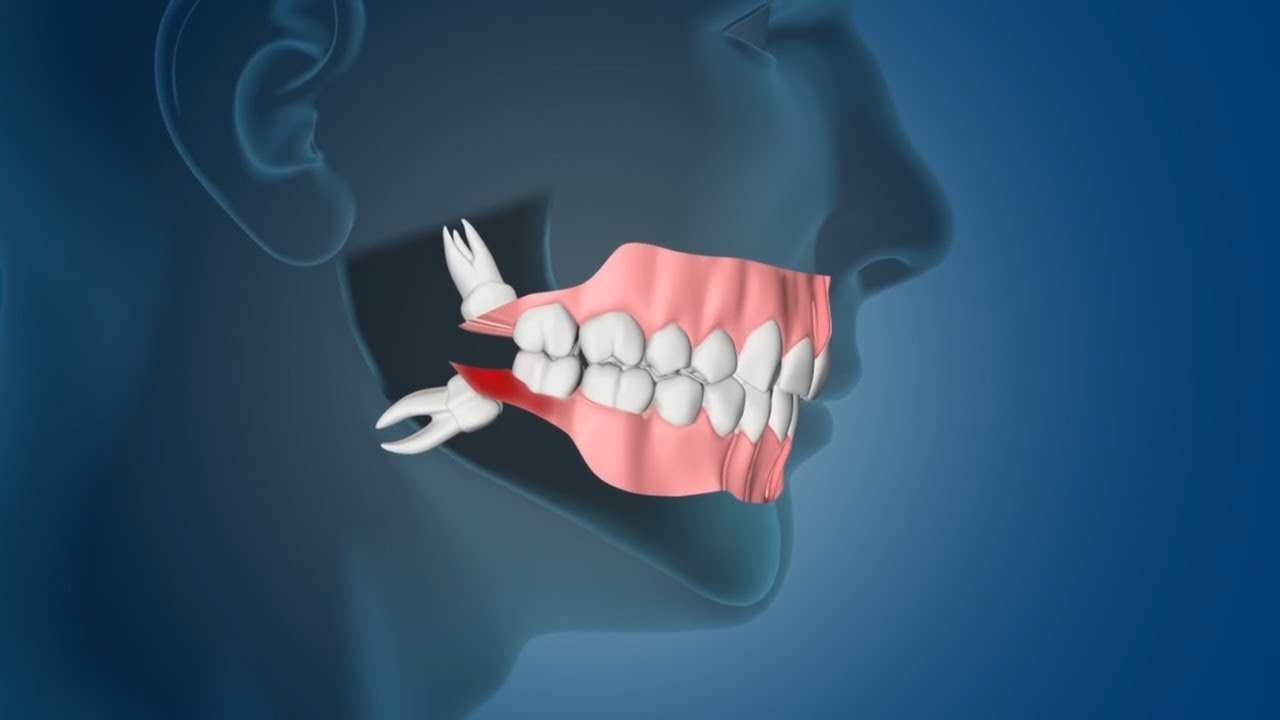

20 Yaş Diş Çekimi

20 yaş dişi; genelde 16-25 yaş aralığında çenenin iki tarafının sonunda olmak üzere toplamda 4 adet çıkan üçüncü büyük azı...

Devamını Oku

Gömülü Diş...

Gömülü dişler, ağız cerrahisinde en sık görülen olgulardır. Ağızda sıklıkla alt-üst 20 yaş dişleri, üst çene köpek dişleri ve...